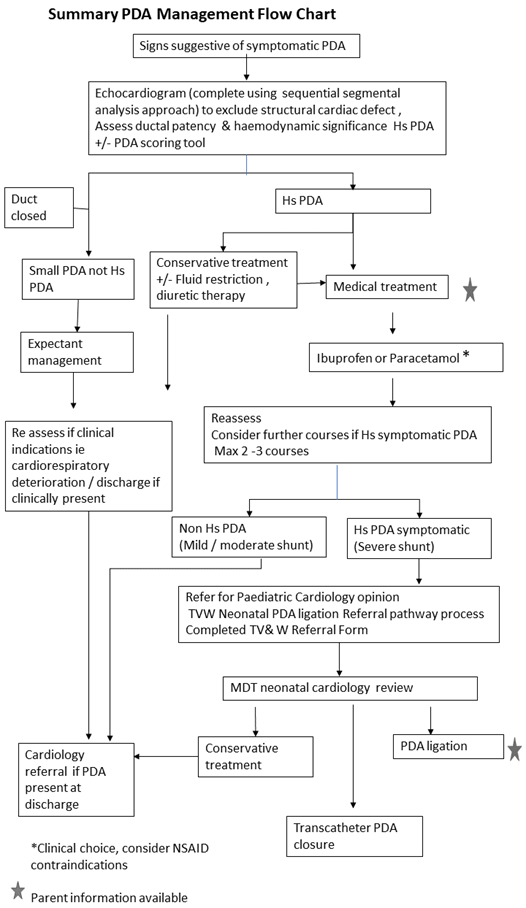

PDA Pathophysiology and Anatomy

Surgical closure Neonatal PDA PPT

Management of PDA infants who received IVH prophylaxis PDA Patent

Text Patent Ductus Arteriosus PDA in Premature Infants

PATENT DUCTUS ARTERIOSUS PDA IN CHILDREN Dr Gaurav Agrawal

Patent Ductus Arteriosus PDA in the newborn

PDA in Preterm Infants Neonatal Network South East

Algorithm for management of PDA in infants with birth weight 800 g